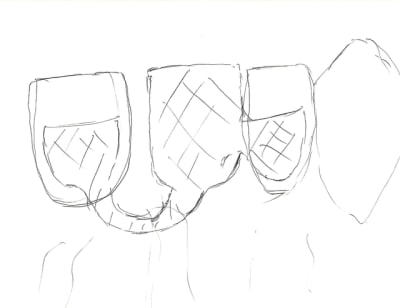

ya ça aussi ailette collée coulée par le prothésiste avec un bord passant près de la papille rétroincisive pour laisser le diastème

désolé pour la qualité du dessin